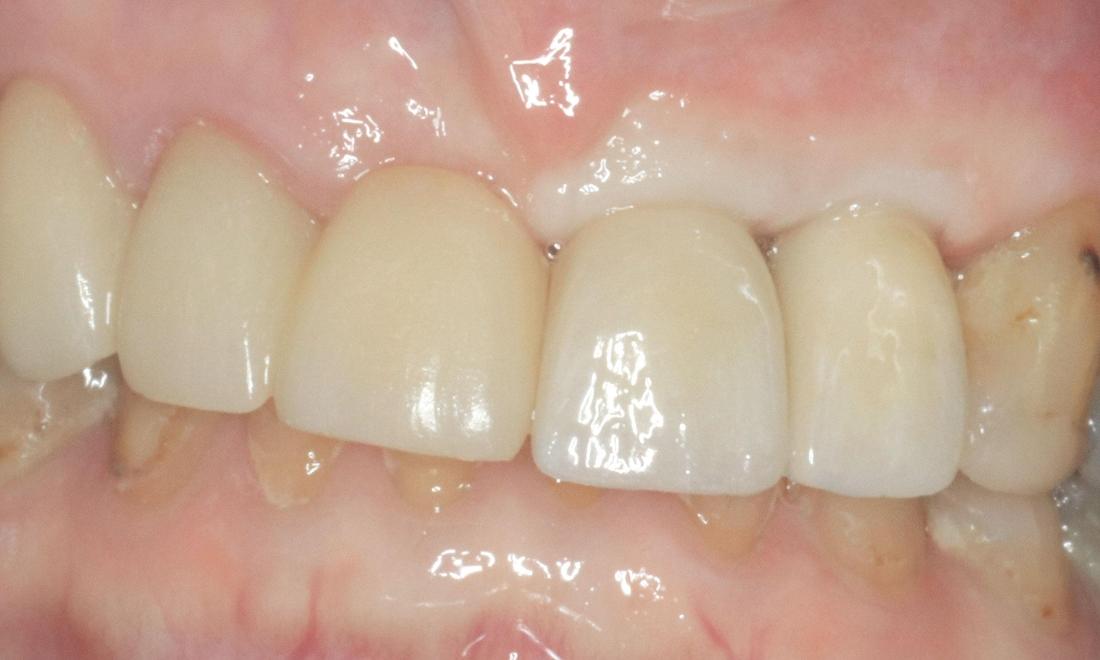

An elderly patient had a dental bridge replacing a missing front tooth for many years. The dental bridge failed as the anchor tooth snapped at gum line resulting in two missing teeth. Two options were discussed i.e. removable denture (plate) or implant-supported teeth.

The patient decided to go with implant-supported teeth. The snapped tooth was removed at the same time placing two dental implants. Three months following dental implant placement, two front teeth were secured individually to dental implants in Armidale, NSW. The total treatment time was 3 months.